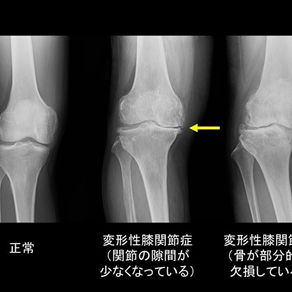

膝が痛い...でも変形じゃない?知られざる“使い方”の問題

「レントゲンで異常はないと言われたのに、膝が痛い」そんなお悩みはありません か? それは骨の問題ではなく、日常の“使い方”に原因があるかもしれません。正しい歩 行・階段昇降・立ち座り動作に着目したリハビリを行うことで、大幅な改善が期待でき ます。 ✅ 変形性膝関節症でなくても痛みは出る! 関節のゆるみ、股関節や足関節の可動域不足、足底アーチの崩れ など、膝は他部位 の影響を大きく受けます。 【実例】60 代女性:膝の屈伸時に痛みあり。歩行指導と骨盤の可動性改善、足底板 併用で週 2 回×3 ヶ月の施術後、階段の昇降が楽になったと報告。 ✅ RehaRISE の評価方法とアプローチ 関節可動域、筋力、荷重バランス、動作分析をもとに、再現性のある評価を実施。個 別に適した 運動療法 を導入します。 ✅ 日常生活で気をつけたい動作トップ 3 1.椅子から立ち上がるときの膝前突 2.階段の踏み込み時の内股動作 3.しゃがむときの足裏不均等荷重 ✅ 目指すは“もう痛みを気にしない生活” 最幸目標は「旅行でたく